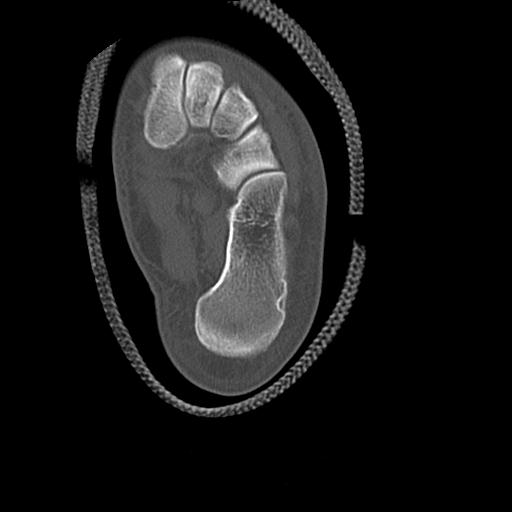

56476 8/28 4R 1/21 2R 左足関節 デジカメ写真 72歳女性 右足関節AS

102755 1/4 2R 1/15 2R 右足関節 68歳女性 右三果脱臼骨折

103177 3/11 右足 2R 3/16 右足 2R リスフラン脱臼 55歳男性